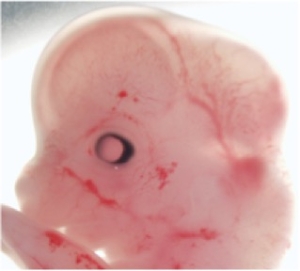

Stage

Stage:

CfS

Day:

d6